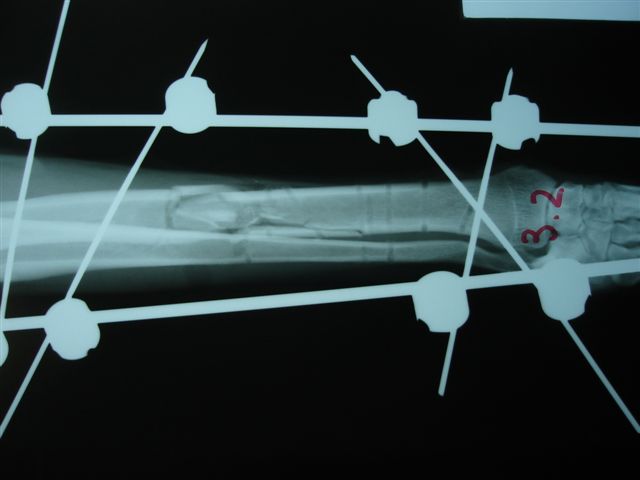

Fijación Externa en IVOT

Fijación Externa

IX CURSO BASICO DE FIJACION EXTERNA.

Casos prácticos alumnos.